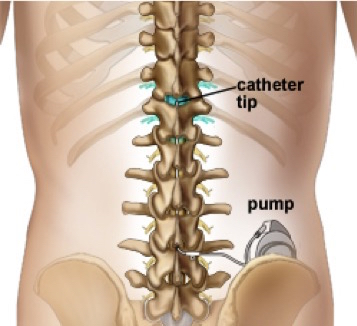

- Intrathecal Pump